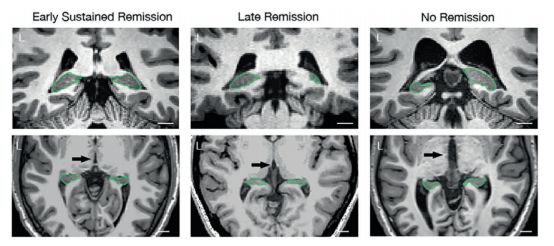

识别临床上有效的神经影像生物标记来预测重度抑郁症患者的治疗反应十分有挑战性,部分原因在于此类研究结果的重复性与应用性都较差。先前研究表明,抑郁症患者的海马体后部体积可能与抗抑郁药疗法的疗效有关。本研究的主要目的是进一步检测抗抑郁药治疗后海马体后部体积是否能预测症状的缓解。研究对196名MDD患者及110名健康被试进行了磁共振成像(MRI)扫描,患者一并接受了为期16周的药物非盲治疗。此数据被纳入了加拿大抑郁症生物标记整合网络计划的第一项研究 (first study in the Canadian Biomarker Integration Network in Depression program, CAN-BIND 1)。海马体体积采用了手工分区及FreeSurfer 6.0来测量。与健康被试相比,抑郁症患者的基线海马体尾部(hippocampal tail, Ht)体积明显较小。基线时较大的Ht体积与第8周及第16周的症状缓解水平呈正相关。与在第16周之前症状未得到缓解的参与者相比,自早期开始症状持续缓解的参与者的Ht体积明显更大。Ht体积是MDD患者抗抑郁药疗效的有效预后生物标记。

MDD患者的海马体尾端体积不成比例分布的不同形式